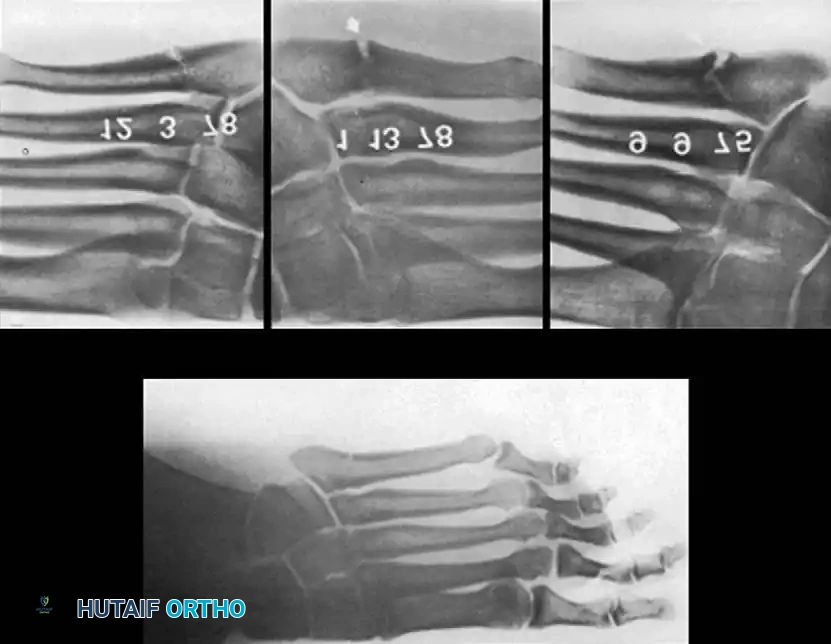

METATARSALS Surgical Diagram

Fig. 86-46 Internal fixation of fifth metatarsal fracture. A and B, Position of the drill bit confirmed with AP and lateral radiographs. C, A 6.5-mm malleolar screw and small iliac cancellous bone graft were utilized due to cortical hypertrophy and a history of repeated fractures. D, Several months post-union, the screw was removed at the patient’s request, though it may remain in place indefinitely.